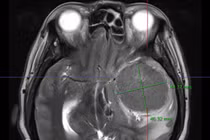

Ca phẫu thuật kéo dài với nhiều thách thức do màng cứng dày dính vào hộp sọ, tuy nhiên ê-kíp đã thành công lấy trọn khối u.

U màng não có thể xảy ra với bất kỳ ai, thường phát triển âm thầm, khi được phát hiện khối u đã có kích thước lớn, người bệnh đối mặt với nhiều biến chứng.